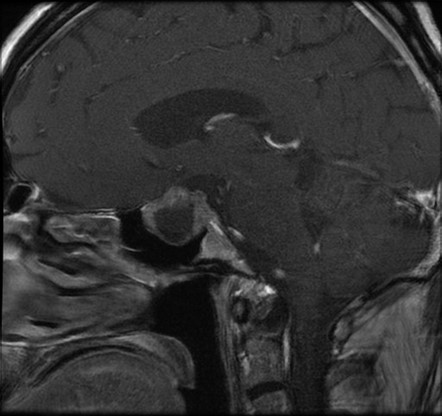

54-year-old man with weight gain and muscle weakness

Results of MRI of the pituitary gland return and are shown:

Which of the following is a correct interpretation of the MRI of the pituitary gland? (Please select only one option.)